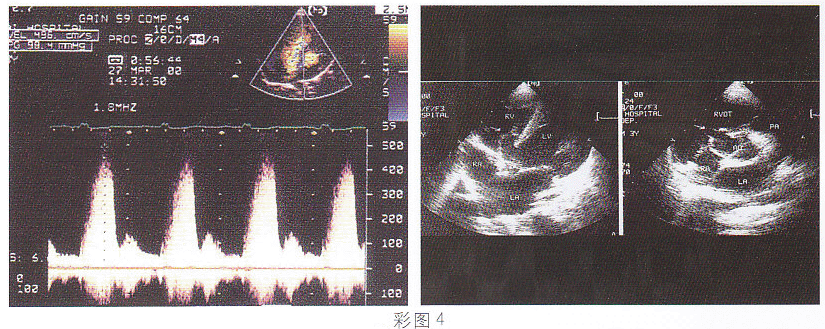

4.該病例最可能的診斷(彩圖4)

正確答案:D 解題思路:室間隔膜部呈瘤樣膨出并見缺損,缺口處探及高速過隔血流信號。